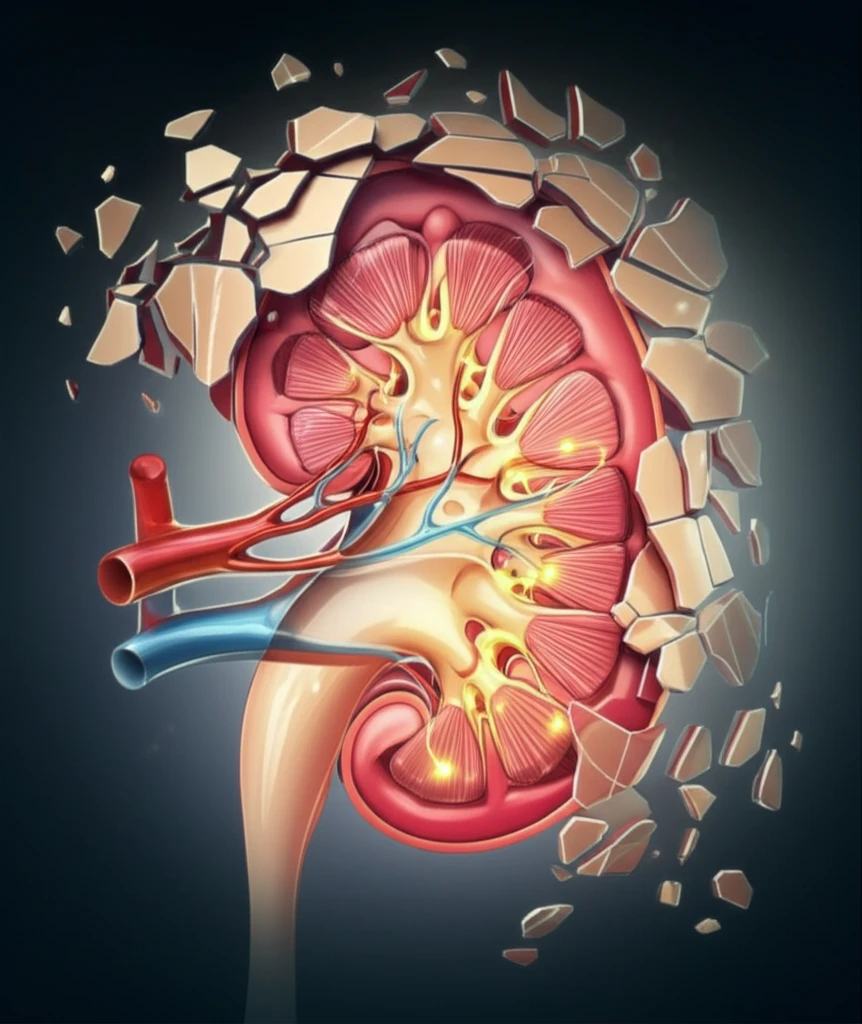

Chronic kidney disease (CKD) affects millions worldwide, often leading to kidney failure and the need for dialysis or transplantation. A major hallmark of CKD is the progressive damage to and loss of podocytes, highly specialized cells in the kidney's glomeruli. These cells are essential for filtering waste from the blood, and once damaged, they are notoriously difficult to regenerate, leading to a decline in kidney function.

For years, researchers have been exploring potential avenues for kidney regeneration, with a particular focus on parietal epithelial cells (PECs) found in Bowman's capsule, a structure within the kidney. The question has been whether these PECs can be coaxed into becoming new podocytes to replace the damaged ones and restore kidney function. The idea is similar to how stem cells work, by being dormant and activating in times of injury.

The study's central finding revolves around the chemokine CXCL12, a signaling molecule known to play a role in various bodily processes, including immune cell trafficking and stem cell maintenance. Podocytes, the kidney's specialized filtration cells, constantly release CXCL12. This release was thought to maintain the quiescence of PECs, preventing them from spontaneously turning into new podocytes.